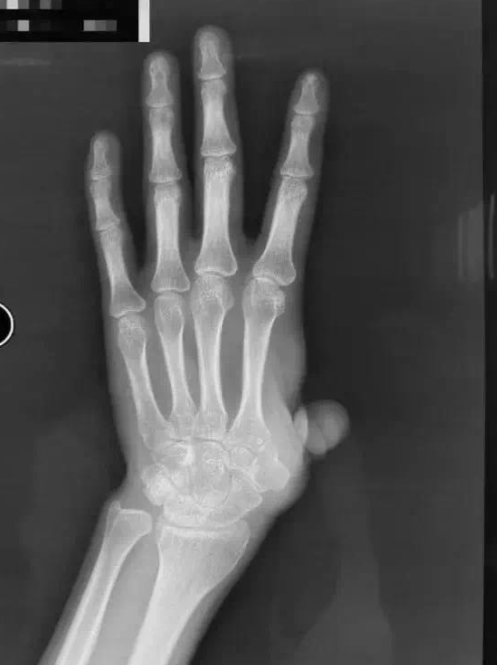

患者因机器伤导致左手拇指在掌骨水平近端离断,在其他医院进行了再植术,但术后手指存活情况欠佳。随后,患者又做了多次手术,但都没有成功保指,左手拇指仅残留部分冗余皮肤,没有掌骨,外观和功能都受到了极大的影响。

为了保住左手功能,患者慕名来到积水潭医院手外科就诊。陈山林检查后发现,他的左手第一系列缺失,若采用传统办法进行拇指再造,不仅重建的掌骨有被吸收掉的风险,而且患者无法获得有功能的腕掌关节。稳定又可活动的腕掌关节恰恰在发挥拇指功能中是最为重要的一环。考虑患者左手仍保留完整的大多角骨,陈山林团队决定为患者定制化制作金属3D打印的第一掌骨,满足患者第一腕掌关节的解剖学重建,为患者的拇指再造提供了一个良好的骨性基础。经文献检索,该技术属于世界首创。

图片已进行处理